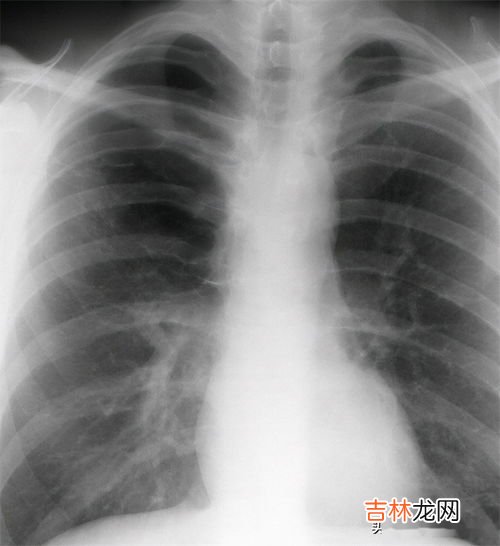

此次放开之后 , 主要是老年人和体质偏弱的二次感染人群出现了“白肺”的现象 。

那是因为他们的呼吸系统对新冠病毒顾安然的清除无效,免疫反应打成了持久战 。

新冠确诊后出现发热或者高烧的情况可以说是常有的事,但是一般吃了退烧药之后,体温都能够在三天之内回到正常的水准 。如果是一直高烧超过39摄氏度 , 并且咳嗽的时候还伴有浓黄痰甚至咳血的情形,那就要重视了 。可能肺里有渗出了 , 建议去医院拍个肺部CT、查个血,不要硬抗 , 避免发生肺炎 。